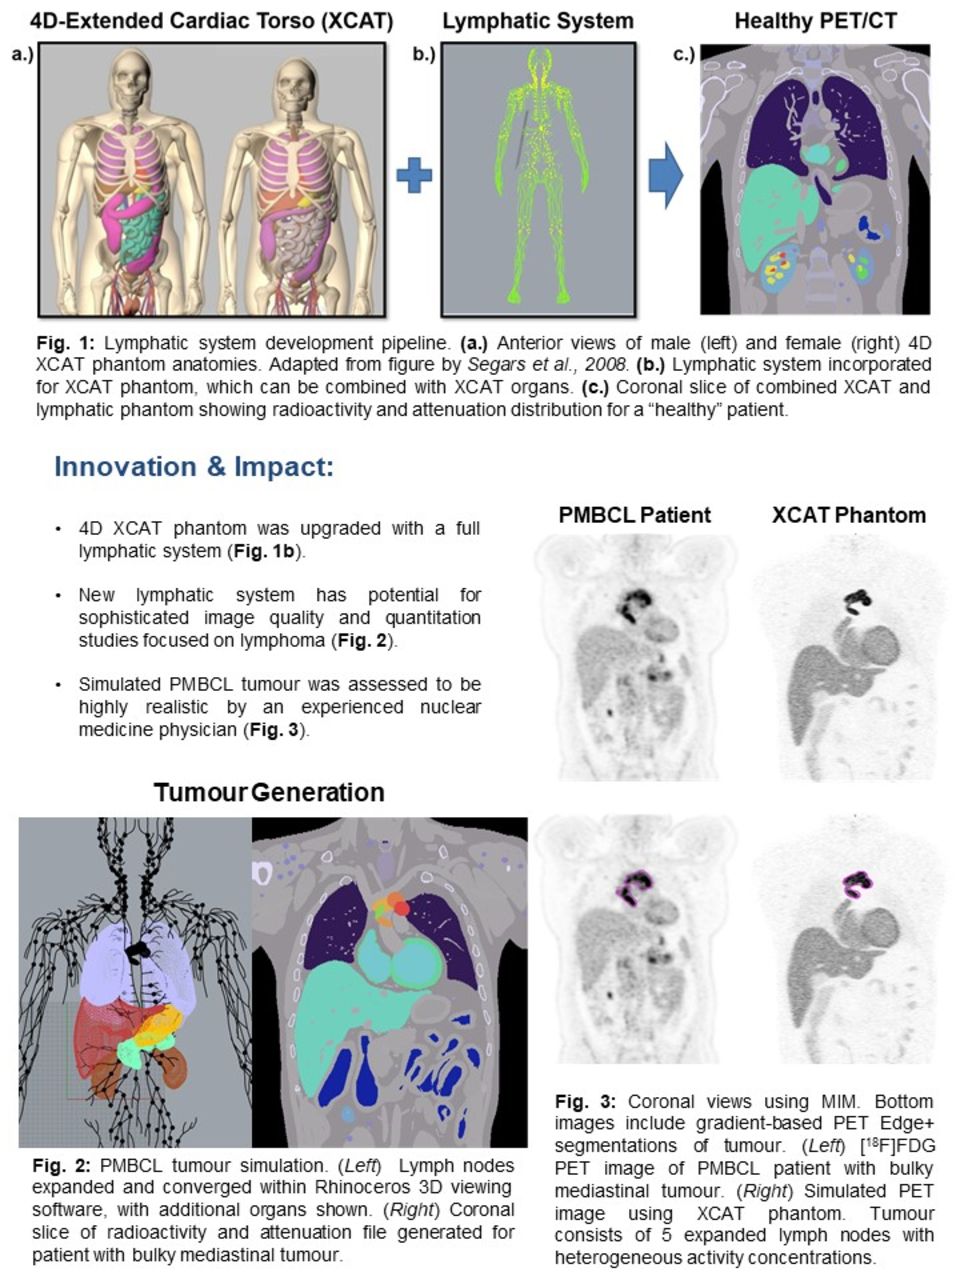

Facilitate learning with our scientific Pet/ct Lymphatic System gallery of hundreds of educational images. accurately representing photography, images, and pictures. perfect for research publications and studies. Browse our premium Pet/ct Lymphatic System gallery featuring professionally curated photographs. Suitable for various applications including web design, social media, personal projects, and digital content creation All Pet/ct Lymphatic System images are available in high resolution with professional-grade quality, optimized for both digital and print applications, and include comprehensive metadata for easy organization and usage. Explore the versatility of our Pet/ct Lymphatic System collection for various creative and professional projects. Multiple resolution options ensure optimal performance across different platforms and applications. Whether for commercial projects or personal use, our Pet/ct Lymphatic System collection delivers consistent excellence. Professional licensing options accommodate both commercial and educational usage requirements. Each image in our Pet/ct Lymphatic System gallery undergoes rigorous quality assessment before inclusion. Time-saving browsing features help users locate ideal Pet/ct Lymphatic System images quickly. Advanced search capabilities make finding the perfect Pet/ct Lymphatic System image effortless and efficient. Comprehensive tagging systems facilitate quick discovery of relevant Pet/ct Lymphatic System content. Instant download capabilities enable immediate access to chosen Pet/ct Lymphatic System images.